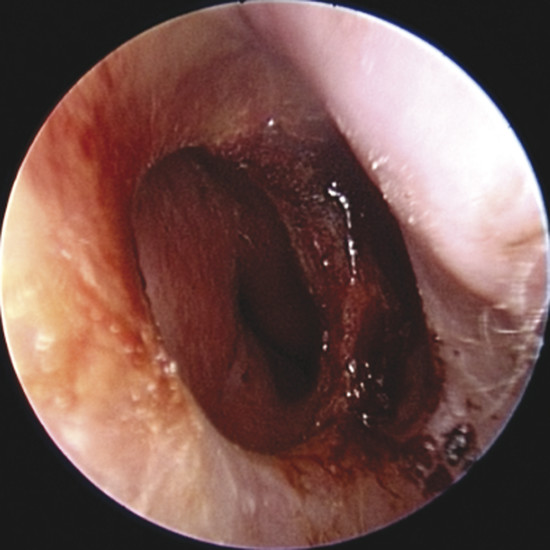

Upon physical examination of the nose, a full diagnosis cannot be made until all crusts have been removed and decongestion of the turbinates has taken place, making it possible to visualize the entire nasal septum. The nasal endoscopy allows appreciating the configuration of the NSP, the presence or absence of adherent crusts on the edges of the defect (Fig. 6‑1), any easily bleeding areas (Fig. 6‑2), and the state of the remaining mucosa, which may present some aspects regarding ischemic conditions (cocaine abuse) (Fig. 6‑3).

In addition, it is possible to measure the size of the NSP under endoscopic control that is critical when choosing the most suitable surgery (Fig. 6‑4).